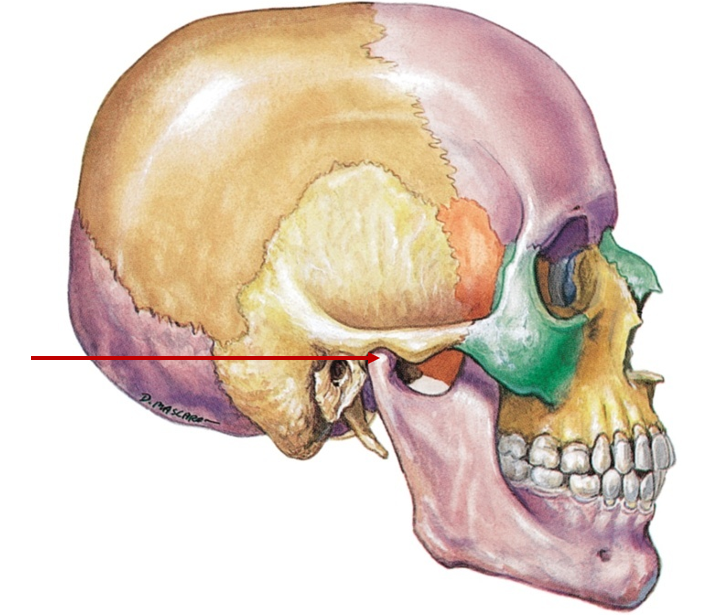

Mandibular fossa

Pocket where jaw connects to skull

Styloid process

Sharp, pointy projection below ear

Mastoid process

Round, bumpy area behind ear

External auditory meatus

Ear canal (sound waves)

Zygomatic process

Projection, connects temporal and zygomatic